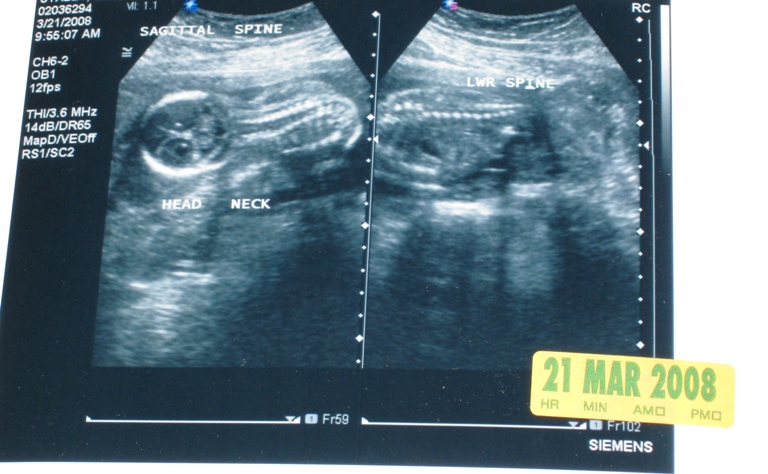

Here are some of the ultrasound pictures. The technician said “All babies look like aliens at 20 weeks.”